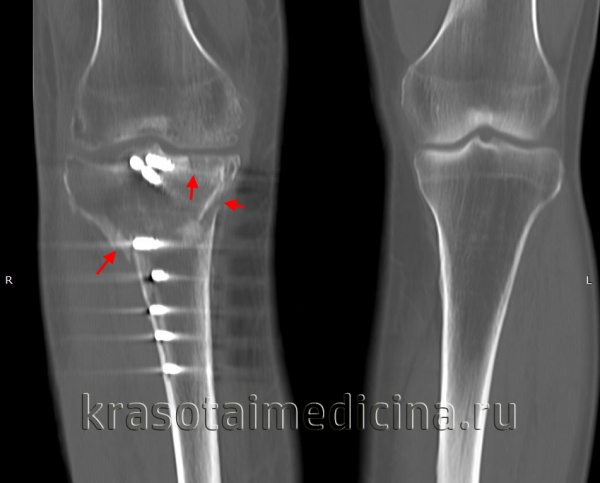

КТ коленных суставов. Внутрисуставной перелом латерального и медиального мыщелков большеберцовой кости